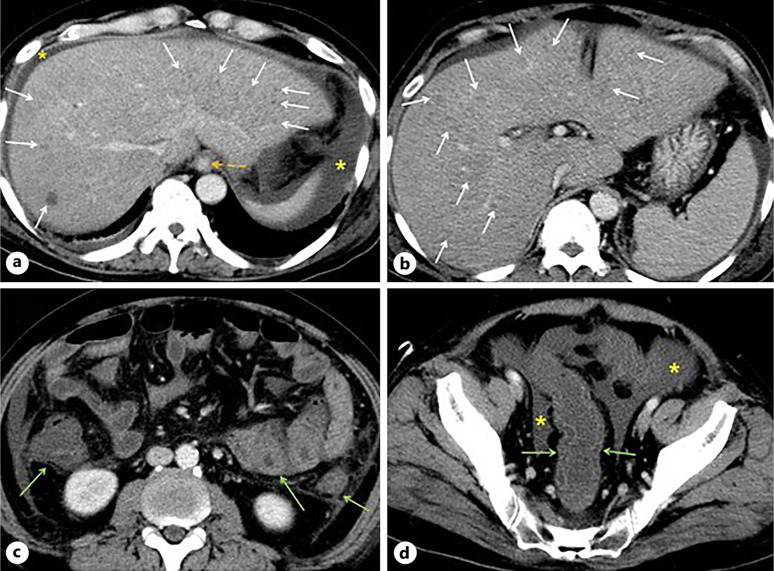

Case presentation: A 54-year-old male presented to the emergency department with motor weakness. He reported experiencing exertional dyspnea and watery diarrhea for the past 3 months, approximately ten times daily. Arterial blood gas analysis indicated hypoxia and hypocapnia compatible with chronic respiratory alkalosis. The transtubular potassium gradient was 1.69, and the aldosterone/renin ratio was 17.6 (ng/dL)/(ng/mL/h). The patient had a 30-year history of consuming 360-720 mL of 20% alcohol almost daily. Abdominal computed tomography revealed multiple regenerative and dysplastic nodules in the liver, splenomegaly, ascites, esophageal varices, and diffuse edematous wall thickening in the bowel, suggesting portal hypertensive enteropathy. Computed tomography of the lungs showed no specific abnormalities in the lungs, pleura, or thoracic wall.